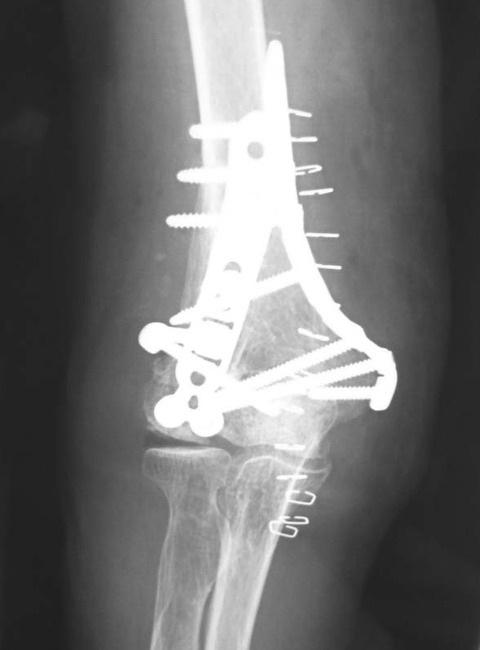

先日、他院で施行された骨折手術の抜釘術を検討する機会がありました。術後2年近く経過しており、骨折部の疼痛等は特にありません。

単純X線像では、骨折部にやや不整な像を認めます。内固定材料はロッキングプレートですが、このような症例では注意が必要だと感じています。